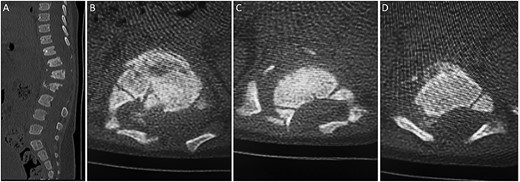

(A) sagittal thoracolumbar CT scan. (B–D) Axial thoracolumbar CT scan. (A-D) There are compression fractures and decreased vertebral body height of T12 and L1 with left pedicle and spinous process fractures. These fractures are associated with bony fragments within the spinal canal causing narrowing of the spinal canal at the same level. There is a nondisplaced fracture at the spinous process of L3 and the left transverse process of T10.

A spine radiograph and CT scan (Figs 1 and 2) revealed a three-column fracture of T12-L1 and an L2 body fracture. A multiplanar and multisequential MR images (Fig. 3) of the whole spine were performed utilizing trauma protocol. The images demonstrated narrowing of the spinal canal at the level of thoracolumbar junction secondary to multilevel fractures along with myelomalacia changes involving the lower thoracic cord and conus medullaris. Additionally, the images showed an evidence of kyphosis measuring 47° at the fracture site.